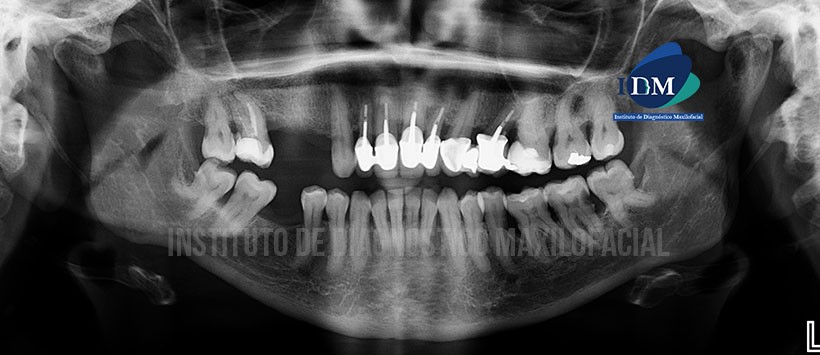

A la evaluación de la radiografía panorámica, se aprecia la mineralización de ambos procesos estilohioideos, placa dental mineralizada en zona cervical de todas las piezas, reabsorción ósea alveolar moderada bimaxilar, piezas con material de obturación de conducto, espigos, coronas, múltiples restauraciones y caries en distal de la pieza 37. Siendo lo más resaltante la dilaceración de las raíces distales de las piezas 38 y 48 respectivamente así como una probable bifurcación del conducto dentario inferior próximo a los ápices de las piezas previamente mencionadas. (Figura 1)

En la evaluación realizada mediante la tomografía volumétrica de haz cónico, se encontró que existe una variante anatómica por parte de ambos conductos dentarios inferiores (bifurcación del conducto sin confluencia). Dichas variantes a su vez tienen un recorrido entre los ápices de las raíces mesiales de las piezas 38 y 48 respectivamente. (Figuras2, Figura 3 y figura 4). También se puede visualizar que el conducto dentario inferior presenta una prolongación hacia la zona sinfisiaria (conducto incisivo)